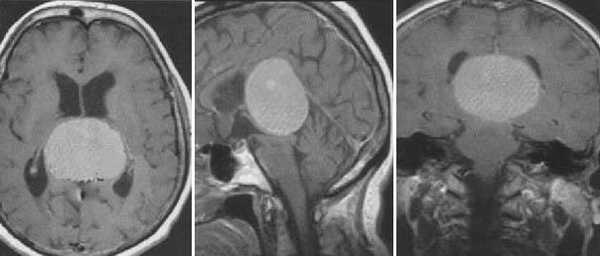

Пинеоцитома. МРТ в режиме Т2 и Т1 выявляется солидного строения опухоль задних отделов III желудочка мозга. На фоне в/в контрастирования определяется выраженный и достаточно гомогенный характер контрастирования опухоли.

Пинеобластома. В режиме Т2 и Т1 выявляется опухоль задних отделов III желудочка мозга с развитием окклюзионной гидроцефалии. В строме опухоли небольшой участок подострого кровоизлияния. После в/в контрастирования опухоль интенсивно и достаточно гомогенно накапливает контрастирующее вещество.

Пиллоидная астроцитома задних отделов III желудочка. Определяется небольших размеров образование с развитием окклюзионной гидроцефалии. Опухоль практически не отличается по сигналам от вещества головного мозга. После в/в контрастирование отмечается усиление МР-сигнала от образование, что позволяет уточнить расположение опухоли, степень компрессии четверохолмной пластинки и водопровода мозга.